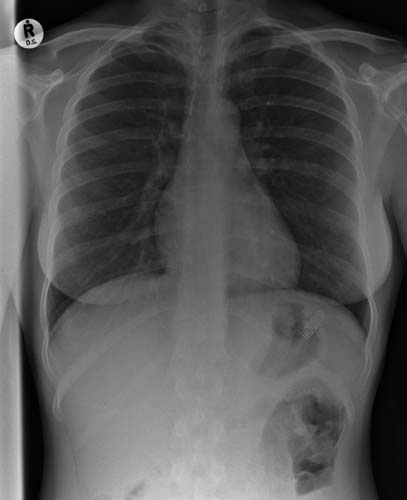

Bu röntgenler gerçek!

Bu röntgenler gerçek! galerisi resim 14

Yutulmuş bir diş fırçası